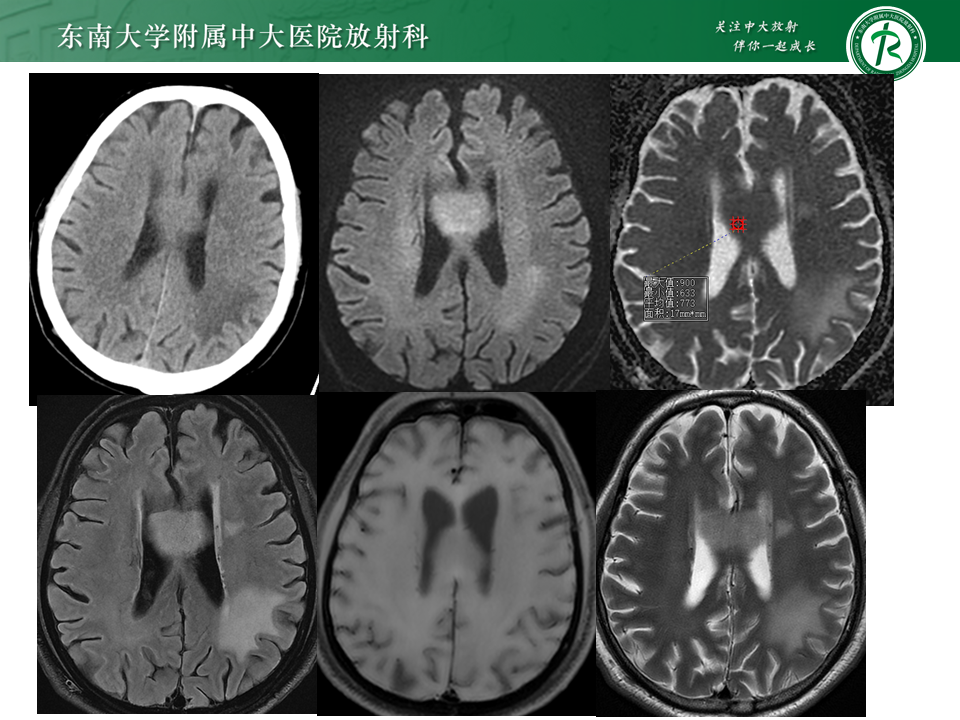

跨中线的脑内占位的影像分析思路